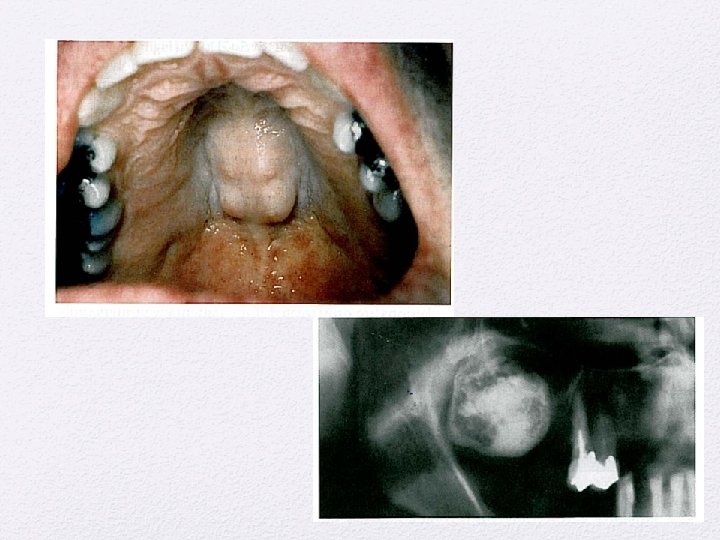

Penyakit pada kelenjar ludah

Lesi reaktif • Mucocelle • Mucus retention cyst • Sialolithiasis • Chronic sclerosing sialadenitis • Necritizing sialometaplasia

Benign salivary gland tumors • Pleomorphic adenoma • Monomorphic adenoma • Papillary cystadenoma lymphomatosusm • Oncocytoma